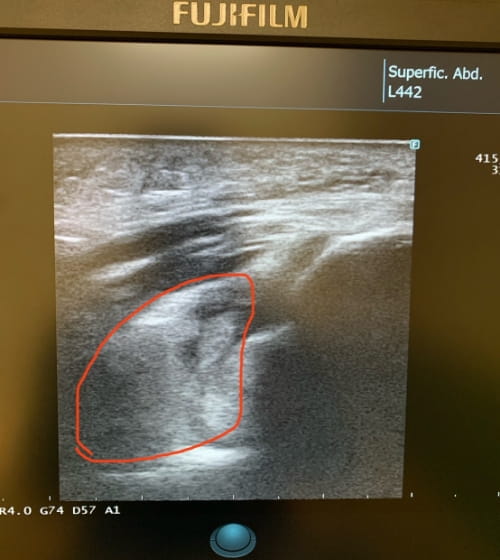

超音波エコー検査で骨折と疑われる画像

整形外科のレントゲンにて骨折は無いと言われていましたが、念のため当院でエコー(超音波)画像による観察を行いました。

その結果「ファットパッドサイン」と呼ばれる、肘関節内に骨折がある可能性を示す所見が確認されました。